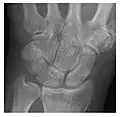

Figure 3: A 26-year-old man presenting with wrist pain after being assaulted. (a) Initial anteroposterior radiograph shows a subtle linear lucency within the scaphoid extending to the scaphocapitate articular surface that was overlooked (arrow). (b) Initial "scaphoid" view was negative. (c) Followup anteroposterior radiographs, 12 days later, shows obvious scaphoid fracture (arrows).[1]

Triquetral fracture usually occurs on the dorsal aspect by impingement from the ulnar styloid or avulsion of strong ligamentous attachment. The dorsal avulsion fracture or "chip fracture" appears as a small bony fragment on the dorsal aspect of the triquetrum and is best detected on the lateral view(Figure 4). When radiography is negative in patients with high suspicion of a fracture, both MRI and MDCT will be of value. However, it has been shown that MRI is superior for detecting trabecular fractures in carpal bones.